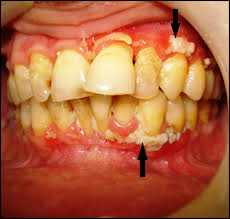

Oral Lesions Pediatrics Harwood Nuss Clinical Practice Of Emergency Medicine 6 Ed

Oral Lesions Pediatrics Harwood Nuss Clinical Practice Of Emergency Medicine 6 Ed from doctorlib.info

The herpes simplex virus is categorized into 2 types: Herpes simplex virus two further conditions, seen especially in children, are herpetic gingivostomatitis and herpetic whitlow. Gingivostomatitis is a combination of gingivitis and stomatitis, or an inflammation of the oral mucosa and gingiva. Herpetic gingivostomatitis is often the initial presentation during the first (primary) herpes simplex infection. Herpes simplex virus infections may be caused by two virus genotypes: